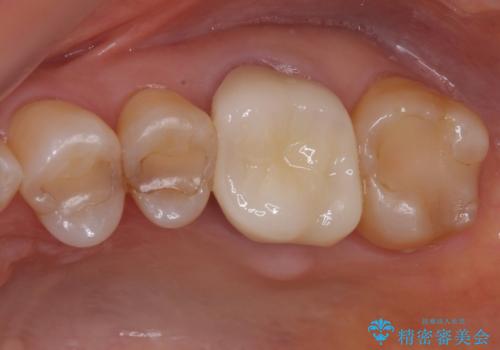

奥歯の被せ物のやり直し 精密根管治療

大きい虫歯 根管治療〜オールセラミッククラウン